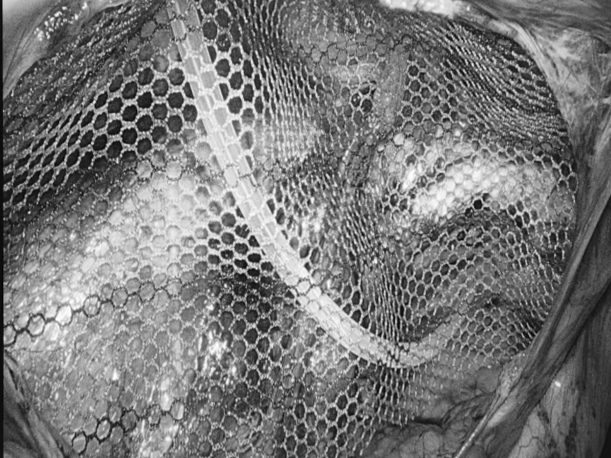

“医生,我爸妈只是关节痛,吃了点止痛药,怎么会胃穿孔要手术?”在普外科病房里,这样的疑问屡见不鲜,很多儿女都困惑不已:明明只是想帮老人缓解疼痛,一片孝心,怎么会把父母送进手术室? 今天,贵州航天医院普外科就来和大家聊聊如何科学、安全地使用止痛药,保护我们脆弱的胃肠,享受健康的生活! 【止痛药咋就把胃吃穿了?】 把胃想象成一个气球,胃黏膜就是内壁,很多止痛药(比如布洛芬、双氯芬酸钠等)会削弱这层内壁,胃酸就像强酸,没了胃黏膜这层内壁保护就会直接腐蚀胃,轻则糜烂、溃疡,重则出血、穿孔。 最危险的是:胃穿孔早期可能只是隐隐作痛、有点胀,容易被当成“老胃病”扛过去,等剧痛发作时,胃里的东西已流进腹腔,危及生命。 【为啥受伤的总是老年人?】 ※胃功能减退:上了年纪,胃黏膜变薄、修复能力下降。 ※多种药同吃:很多老人同时服用降压药、抗凝药,和止痛药叠加,胃根本扛不住。 ※自行用药:怕麻烦不去医院,按老经验或邻居推荐买药,隐患最大。 【安全用药“四要、四不要”】 四要—— ✔要查明原因:疼痛是警报,先看病再吃药,别盲目止痛。 ✔要保护胃:在医生指导下可加用胃黏膜保护剂(如奥美拉唑)。 ✔要饭后吃:务必饭后半小时服用,减少刺激。 ✔要见好就收:不疼了就停药,绝不长期吃。 四不要—— ❌不要自己加量:疼得厉害?找医生,别加药。 ❌不要混着吃:不同止痛药一起吃等于伤害叠加。 ❌不要长期吃:一般疼痛不连续吃超过一周。 ❌不要忽视警报:出现胃部不适、黑便、呕血、剧烈腹痛,立即停药就医! 【对付慢性疼痛,还有其他好办法】 ▶热敷、冷敷:简单有效,很多肌肉关节痛都管用。 ▶理疗、按摩:找正规中医推拿,效果不输止痛药。 ▶温和运动:散步、打太极,增强肌肉力量。 ▶转移注意力:养花、写字、聊天——当你不那么关注“痛”时,痛感往往会减轻。 【给子女的2点提醒】 ※管好药箱:定期清理过期药,搞清楚老人每天在吃什么药。 ※当好翻译:陪老人看病时,说清哪里痛、吃过啥药、效果如何。 止痛药是缓解疼痛的有效工具,但绝非“万能神药”。请一定记住:面对疼痛,“硬扛”不是办法,“乱吃”更是大忌,守护胃肠健康,从科学用药开始。 注:本文仅为健康科普,旨在提高公众用药安全意识,具体用药请务必咨询专业医生,遵医嘱执行。 贵州航天医院普外科专家简介 高大勇 普外科(肛肠外科)学科带头人、名誉主任,主任医师、教授 临床擅长:对中西医结合诊治肛肠学科各种常见病、多发病及疑难杂症等具有丰富的临床经验。 原遵义市第一人民医院(遵义医科大学第三附属医院)、遵义市中医院肛肠科主任。中华中医药学会肛肠分会常委,全国中医肛肠学科名专家,中国健康促进与教育协会肛肠分会常委,中国康复医学会肛肠疾病康复专业委员会常委,中国民间中医医药研究开发协会肛肠分会副秘书长,中国医师协会中西医结合肛肠医师专业委员会常委,国家二级心理咨询师,贵州省第一批中医名医工作指导老师,遵义市名中医,遵义市肛肠学会会长,遵义市肛肠质控中心名誉主任,遵义市中西医结合学会名誉会长,遵义市健康科普专家,原贵州省中西医结合学会肛肠分会副主任委员、贵州省中医肛肠质控中心副主任、遵义市医学会医疗鉴定委员会专家、遵义市卫生系列高评委。发表论文30余篇,主编和参编医学著作5本,主持省级科研课题2项、市级科研课题2项、院级科研课题1项。 梁 跃 普外科党支部书记、主任,主任医师 临床擅长:对普外科各类肿瘤手术具有丰富的临床经验。 毕业于遵义医学院,遵义市医学会小儿外科学分会常务委员,遵义市肛肠协会理事,遵义市医学会核医学分会(第二届)委员会委员;荣获第三期“黔医人才计划”优秀学员称号;主持市级课题1项,完成省级课题1项,在国内各类刊物上发表论文10余篇。 钱科洪 民盟盟员,普外科副主任医师 临床擅长:从事普外科临床工作30余年,对各类普外科疾病的诊治、乳腺、甲状腺、胃十二指肠、结直肠等疾病及疑难杂症具有丰富的临床经验。 毕业于遵义医学院临床医疗系,2009年前往中山大学附属第一医院微创外科进修学习,在国内各专业期刊发表论文数篇。 贵州航天医院普外科简介 基本情况 贵州航天医院普外科成立于1968年,前身属于航天部O61基地3417医院外一科,1998年3417医院、3427医院合并后更名为普外科,下设胃肠外科、肛肠外科2个亚专业科室,拥有在全市较为先进的专科设备和技术,是中国疝病专科联盟单位,贵州医科大学附属医院胃肠外科专科联盟单位。开放床位40张,配备医护人员21人。 专科特色 普外科致力于胃肠及肛肠疾病的外科临床诊治及科研,以腹腔镜微创外科技术为本,形成以快速康复治疗胃肿瘤、结直肠肿瘤、小肠肿瘤、直肠脱垂、肥胖病、急腹症、各类疝、痔、瘘等专科特色,同时注重胃肠疾病尤其是结直肠恶性肿瘤的基础研究和临床转化研究,总体诊断和治疗水平在区域同级医院居于领先水平。 开展手术:腹腔镜下胃癌根治术,腹腔镜下袖状胃切除术,腹腔镜下胃肠道间质瘤切除术,腹腔镜下结、直肠癌根治术,胃癌、结直肠癌的精准治疗,腹腔镜下小儿疝气、成人疝修补术,腹腔镜下阑尾手术,内痔的硬化注射治疗及痔疮的微创治疗:ATH、PPH、TST,直肠脱垂的各种手术治疗,难治性伤口VSD技术,鼻胃肠管、肠梗阻导管置入术,肛肠术后间歇性导尿技术,并引进了中医适宜技术,也为各种化疗患者提供输液港安装,提高患者就医体验。 腹腔镜下腹股沟疝 无张力修补术 腹股沟疝里金斯坦 (Lichtenstein)手术 PPH微创术治疗环状混合痔 黏连性或炎性肠梗阻-肠梗阻导管 腹腔镜袖状胃切除 腹腔镜阑尾切除术 腹腔镜阑尾肿瘤切除术 腹腔镜下结肠癌根治术 诊疗范围 胃肿瘤、结直肠肿瘤、小肠肿瘤、肥胖症、各类急腹症、腹部外伤、腹壁疝、便秘、直肠脱垂、痔疮、肛瘘、肛裂等胃肠、肛肠外科疾病。 END